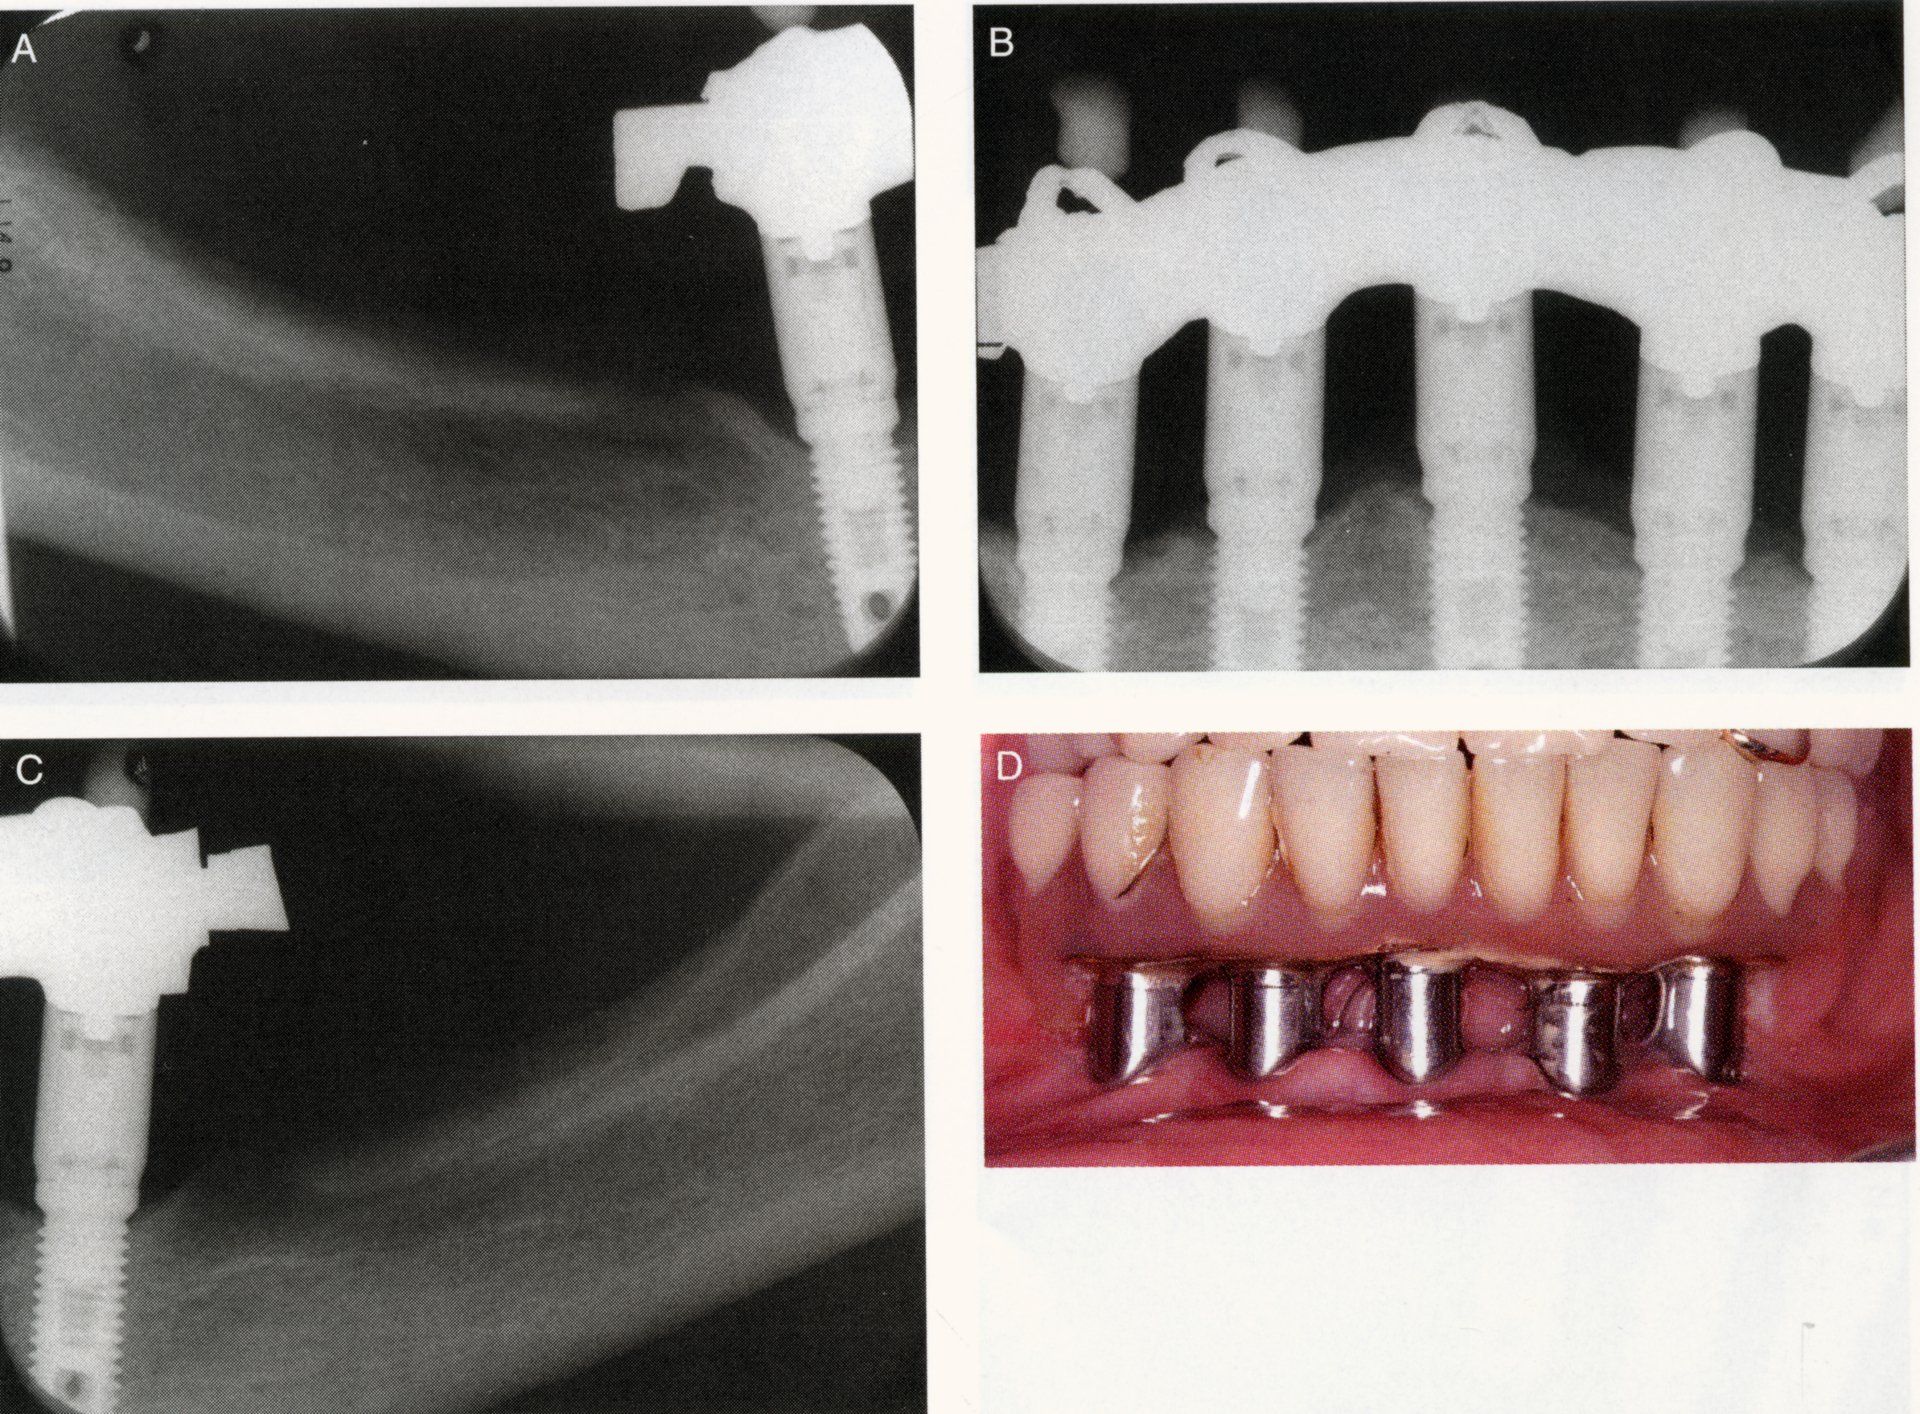

È necessario effettuare una visita che consentirà, in seguito a radiografie, calchi in gesso e fotografie, di effettuare nel dettaglio un’analisi preliminare del singolo paziente.

Generalmente, la procedura di posizionamento delle protesi dentali viene effettuata in due fasi:

- il dentista inizia installando l’impianto, che è stato lasciato da tre a sei mesi a guarire e integrarsi con l’osso mascellare;

- al paziente viene poi installata una protesi provvisoria fino a quando non viene posizionata la corona permanente.